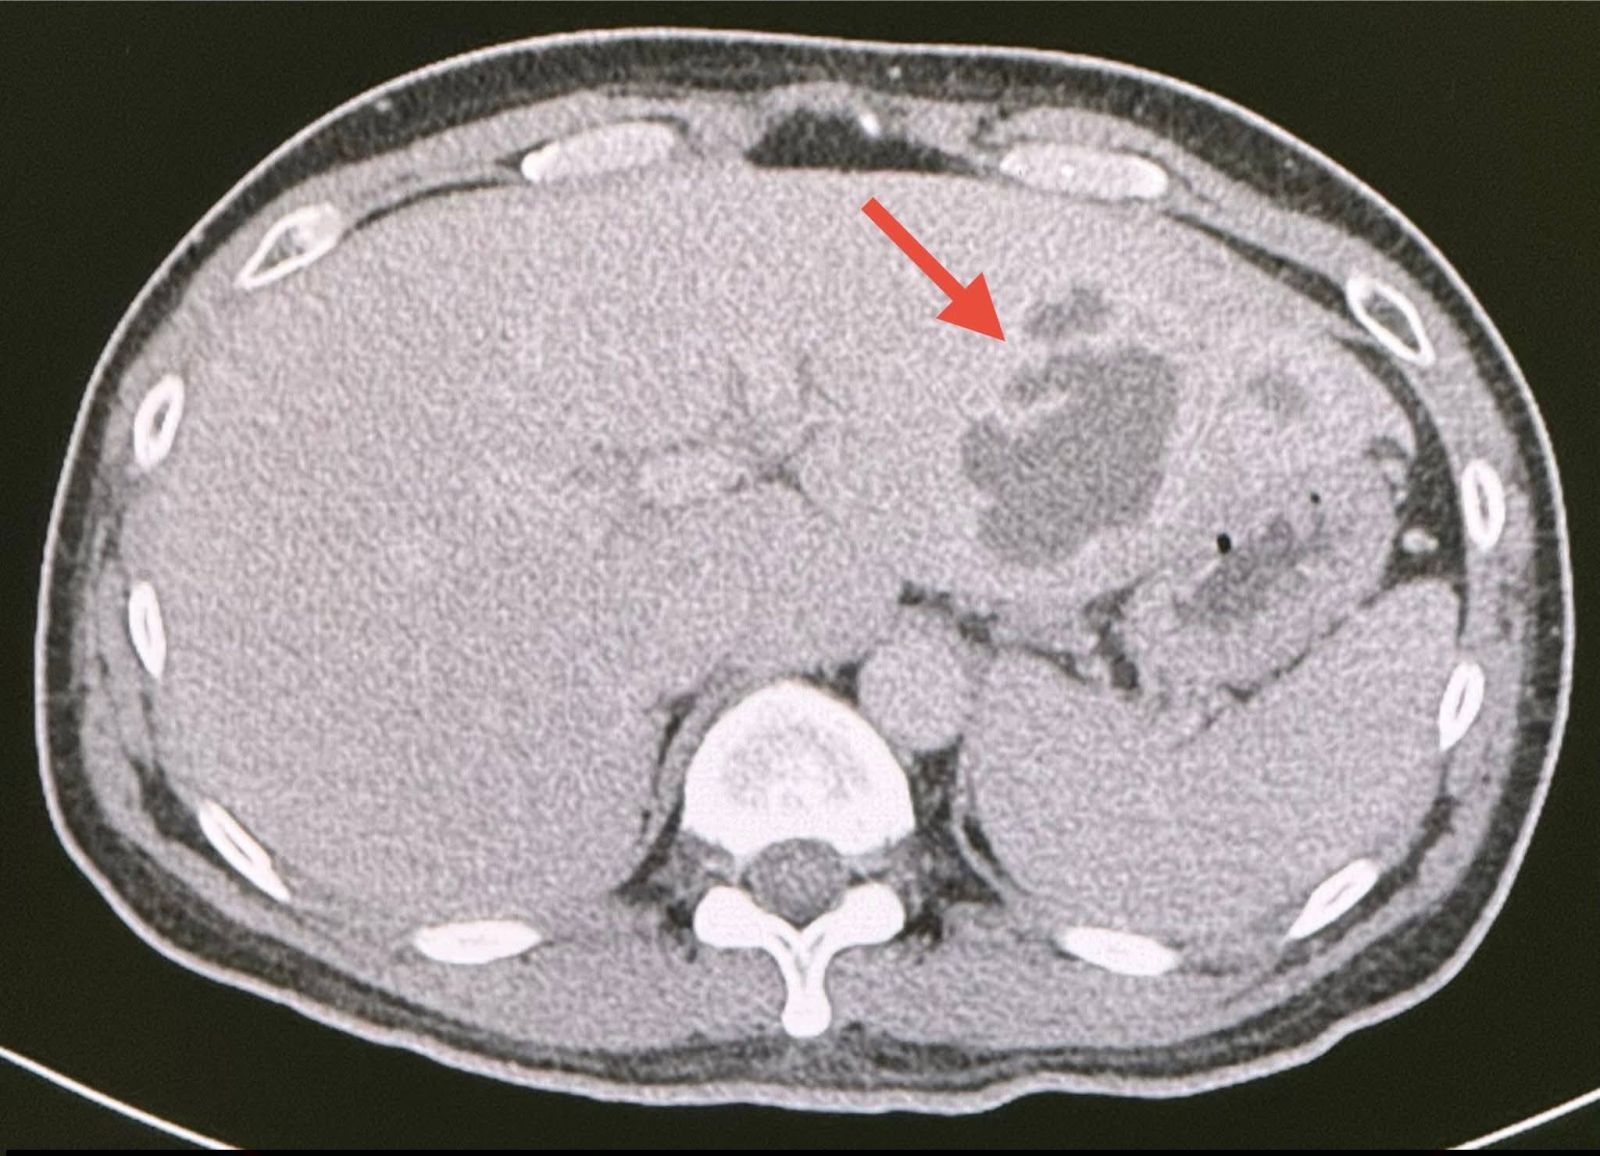

เจาะเลือด เม็ดเลือดขาวในเลือดสูง 15,050 ค่า alkaline phosphatase สูง 564 ส่งเลือดเพาะเชื้อ ไม่ขึ้นเชื้อแบคทีเรีย ทำอัลตราซาวด์ช่องท้อง สงสัยฝีในตับข้างซ้ายขนาด 5.2 × 4 เซนติเมตร ทำคอมพิวเตอร์ช่องท้อง เห็นฝีขนาดใหญ่ในตับด้านซ้ายขนาด 6.6 × 4.3 เซนติเมตร (ดูรูป)

วินิจฉัย: ฝีในตับขนาดใหญ่ในคนที่เป็นโรคเบาหวาน